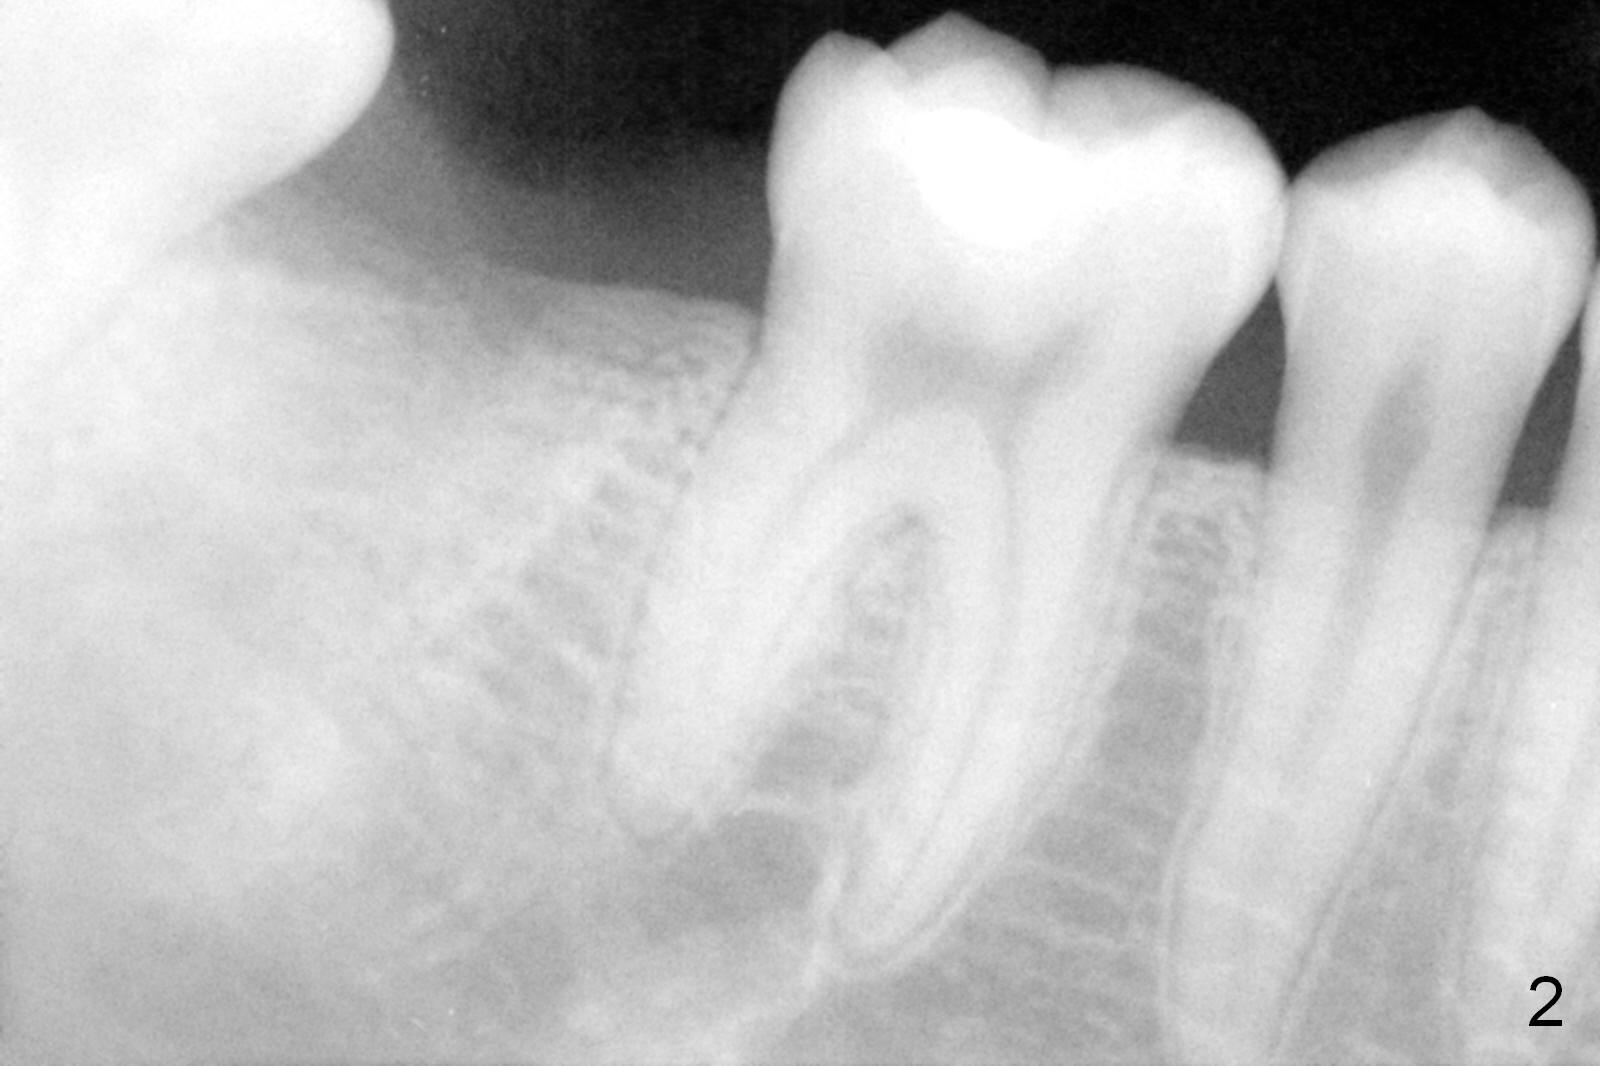

A 22-year-old man (HW) had #31 extracted without bone graft in other office 2 months ago. The socket appears to have healed asymptomatic. Pre-extraction panoramic X-ray shows periapical radiolucency (Fig.1 <). It is unknown that the lesion was eradicated during extraction or not. To reduce post-implant infection (1,2), oral antibiotic is to be taken preop and the osteotomy, once formed, will be treated with an antibiotic (Clindamycin or Metronidazole) or placebo (2% Xylocaine, 1:50,000 Epinephrine). If autogenous bone is harvested from the osteotomy, the bone will be mixed with an agent before placement. A case will be selected if extraction occurs less than 6 months. The 1st case is assigned to Clindamycin group, the present case to Metronidazole, the next to control as shown below.

PA in Fig.2 is taken 2 months post extraction, while Fig.3 shows design of a 5.9x14 mm bone-level implant. It appears that the implant is a little too long (red dashed line: the superior border of the Inferior Alveolar Canal). Initial osteotomy depth will be 12 mm. In fact the implant was designed to be supracrestal distal (mistake, even if bone graft is well executed). An incision will be made for visibility.